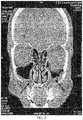

FIG. 2 is a CT scan image of a patient exhibiting symptoms of sinusitis.

FIG. 1 illustrates a comparison between a healthy sinus and a sinus with sinusitis. The sinusitis can cause excess mucous in the frontal sinus and maxillary sinus. Other symptoms can include inflamed sinus lining and a sinus infection.FIG. 2 illustrates a CT image of a patient with chronic sinusitis. The arrows indicate the congested sinuses typical of chronic sinusitis.